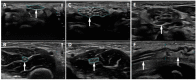

(1) Background: Carpal tunnel syndrome (CTS), a compressive mononeuropathy of the median nerve at the wrist, is rare in childhood and occurs most frequently due to secondary causes. (2) Methods: Medical history, electrodiagnostic findings, and imaging data of patients with CTS from two pediatric neuromuscular centers were analyzed retrospectively. The etiology of CTS was investigated and compared with the literature. (3) Results: We report on a cohort of 38 CTS patients (n = 22 females, n = 29 bilateral, mean age at diagnosis 9.8 years). Electrodiagnostic studies of all patients revealed slowing of the antidromic sensory or orthodromic mixed nerve conduction velocities across the carpal tunnel or lack of the sensory nerve action potential and/or prolonged distal motor latencies. Median nerve ultrasound was diagnostic for CTS and confirmed tumorous and vascular malformations. Etiology was secondary in most patients (n = 29; 76%), and mucopolysaccharidosis was the most frequent underlying condition (n = 14; 37%). Idiopathic CTS was rare in this pediatric cohort (n = 9; 24%). (4) Conclusion: Since CTS in childhood is predominantly caused by an underlying disorder, a thorough evaluation and search for a causative condition is recommended in this age group.